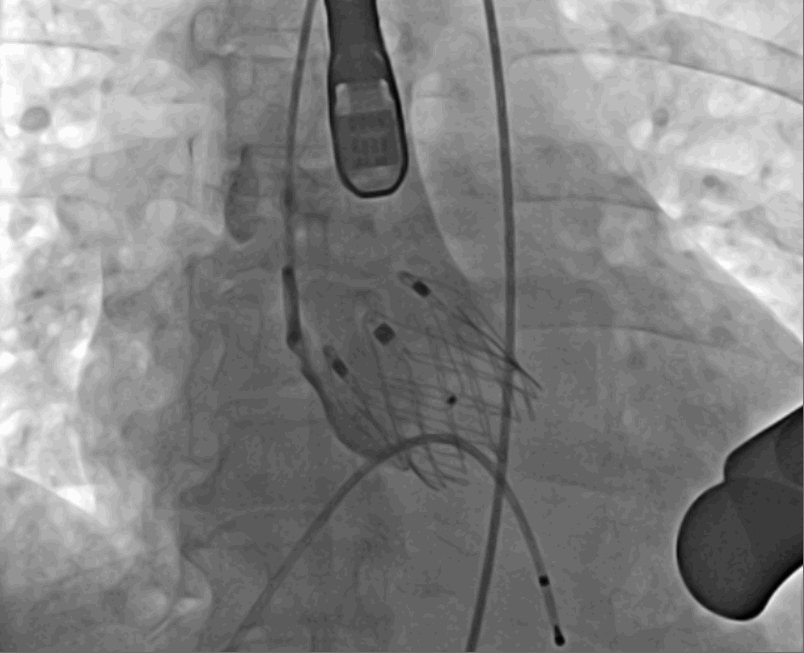

術(shù)前超聲影像圖

該例患者為62歲,女性,因“間歇性心悸、胸悶、氣短、胸痛1年,加重1周”之主訴入院。入院診斷:主動(dòng)脈瓣重度關(guān)閉不全,二尖瓣、三尖瓣輕度關(guān)閉不全,心功能III級(jí);冠狀動(dòng)脈粥樣硬化性心臟病。行心臟超聲心動(dòng)圖提示“主動(dòng)脈瓣重度關(guān)閉不全;瓣口水平以下左室下壁、后下壁搏幅減低;EF值 0.30,左房、左室大、右房大小正常高限;二尖瓣、三尖瓣關(guān)閉不全;輕度肺動(dòng)脈高壓(收縮壓42mmHg);主動(dòng)脈硬化;左室收縮功能重度減低。經(jīng)心血管外科劉洋、楊劍教授、麻醉科陳敏教授及超聲科孟欣教授等專家團(tuán)隊(duì)綜合評(píng)估,判定患者為外科手術(shù)高危患者。